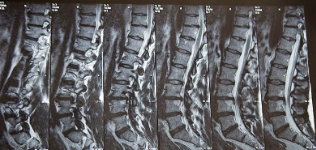

추간판 탈출증 증상 원인 치료방법 추간판 탈출증이란? 알아봐요 추간판 탈출증 증상 원인 치료방법 등 추간판 탈출증에 대해 정리해드리도록 하겠습니다.추간판 탈출증은 디스크가 추간판이라는 구조 안에서 벗어나서 주변 신경을 자극하고 인대를 압박하여 통증을 유발하는 질환입니다. 흔한 증상으로는 허리나 목 부근에서 나타나는 통증, 저림 혹은 근육 경련 등이 있습니다. 원인으로는 나이가 들어서 디스크가 쇠약하여 벗어날 수 있거나, 급격한 강한 충격이나 부드럽지 못한 동작 등으로 인해 디스크가 손상되어 추간판 밖으로 벗어나는 것이 있습니다. 치료는 통증 완화와 함께 특별한 재활 치료 및 수술을 포함할 수 있습니다.

추간판 탈출증은 디스크가 추간판이라는 공간에서 벗어나서 주변 신경을 자극하거나 인대를 압박하여 통증을 유발하는 질환입니다. 이러한 증상은 일반적으로 허리, 목, 어깨 및 다리와 같은 부위에서 나타납니다. 아래는 추간판 탈출증의 일반적인 증상입니다.